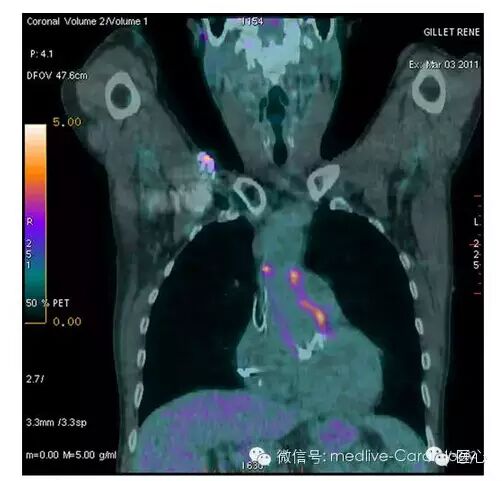

对主动脉狭窄严重程度的评估依然是个难题。主动脉瓣面积(AVA)测量误差的最大来源是左室流出道(LVOT)测量值的变异性,且左室流出道并非圆形,而是椭圆形。莱顿市的研究者对191例经导管主动脉瓣植入(TAVI)且主动脉瓣面积指数(AVAi)<0.6 cm2/m2及LVEF≥50%的患者进行了分析。研究者根据受试者的血流(每搏输出量<35或≥35 mL/m2)及跨瓣压差(≤40或 >40 mmHg)对其进行了分组,并利用多检测器计算机断层扫描(MDCT,图1)测面法测量了受试者的左室流出道面积,联合多普勒血流动力学检查结果得出了融合AVAi。通过使用融合AVAi,52%正常血流低跨瓣压差组患者被重新分至中度病变组;12%低血流低压差组患者被重新分至中度病变组。这种再分类对治疗有重要影响,因为LVEF保留的正常血流低压差的严重主动脉狭窄患者的存活时间与中度主动脉狭窄患者类似,但低血流低压差组患者的存活时间更短。研究表明,融合成像有助准确评估主动脉狭窄患者的病变程度,尤其是在LVEF保留的低血流低压差患者中。

左室流出道测量值(A),经胸超声心动图测量左室流出道直径(B),MDCT测量左室流出道面积(C)(点击查看大图)